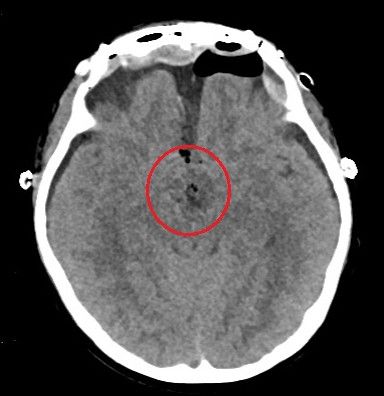

术后头部ct显示:鞍区肿瘤基本切除干净。(红圈内为手术区域)